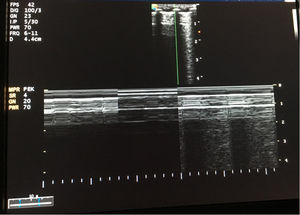

A 4-month-old, ex-premature (24 weeks of pregnancy) patient with severe bronchopulmonary dysplasia on mechanical ventilation (pressure control mode with PIP 25cmH2O, PEEP 5.5cmH2O, respiratory frequency 35rpm and FiO2 30%). On the reported day, the patient required FiO2 of up to 50%, and the chest X-rays (Fig. 1) showed intense hyperinsufflation of the right hemithorax and the absence of the lung sliding sign at pulmonary ultrasound (Fig. 2). In view of the evolution of patients with bronchopulmonary dysplasia towards dynamic compression of the distal airway, we decided to progressively increase PEEP, without ultrasound improvement until PEEP 10cmH2O was reached; at this point pleural sliding was seen to reappear (Fig. 3) and the chest X-rays showed partial resolution of the overdistension (Fig. 4).